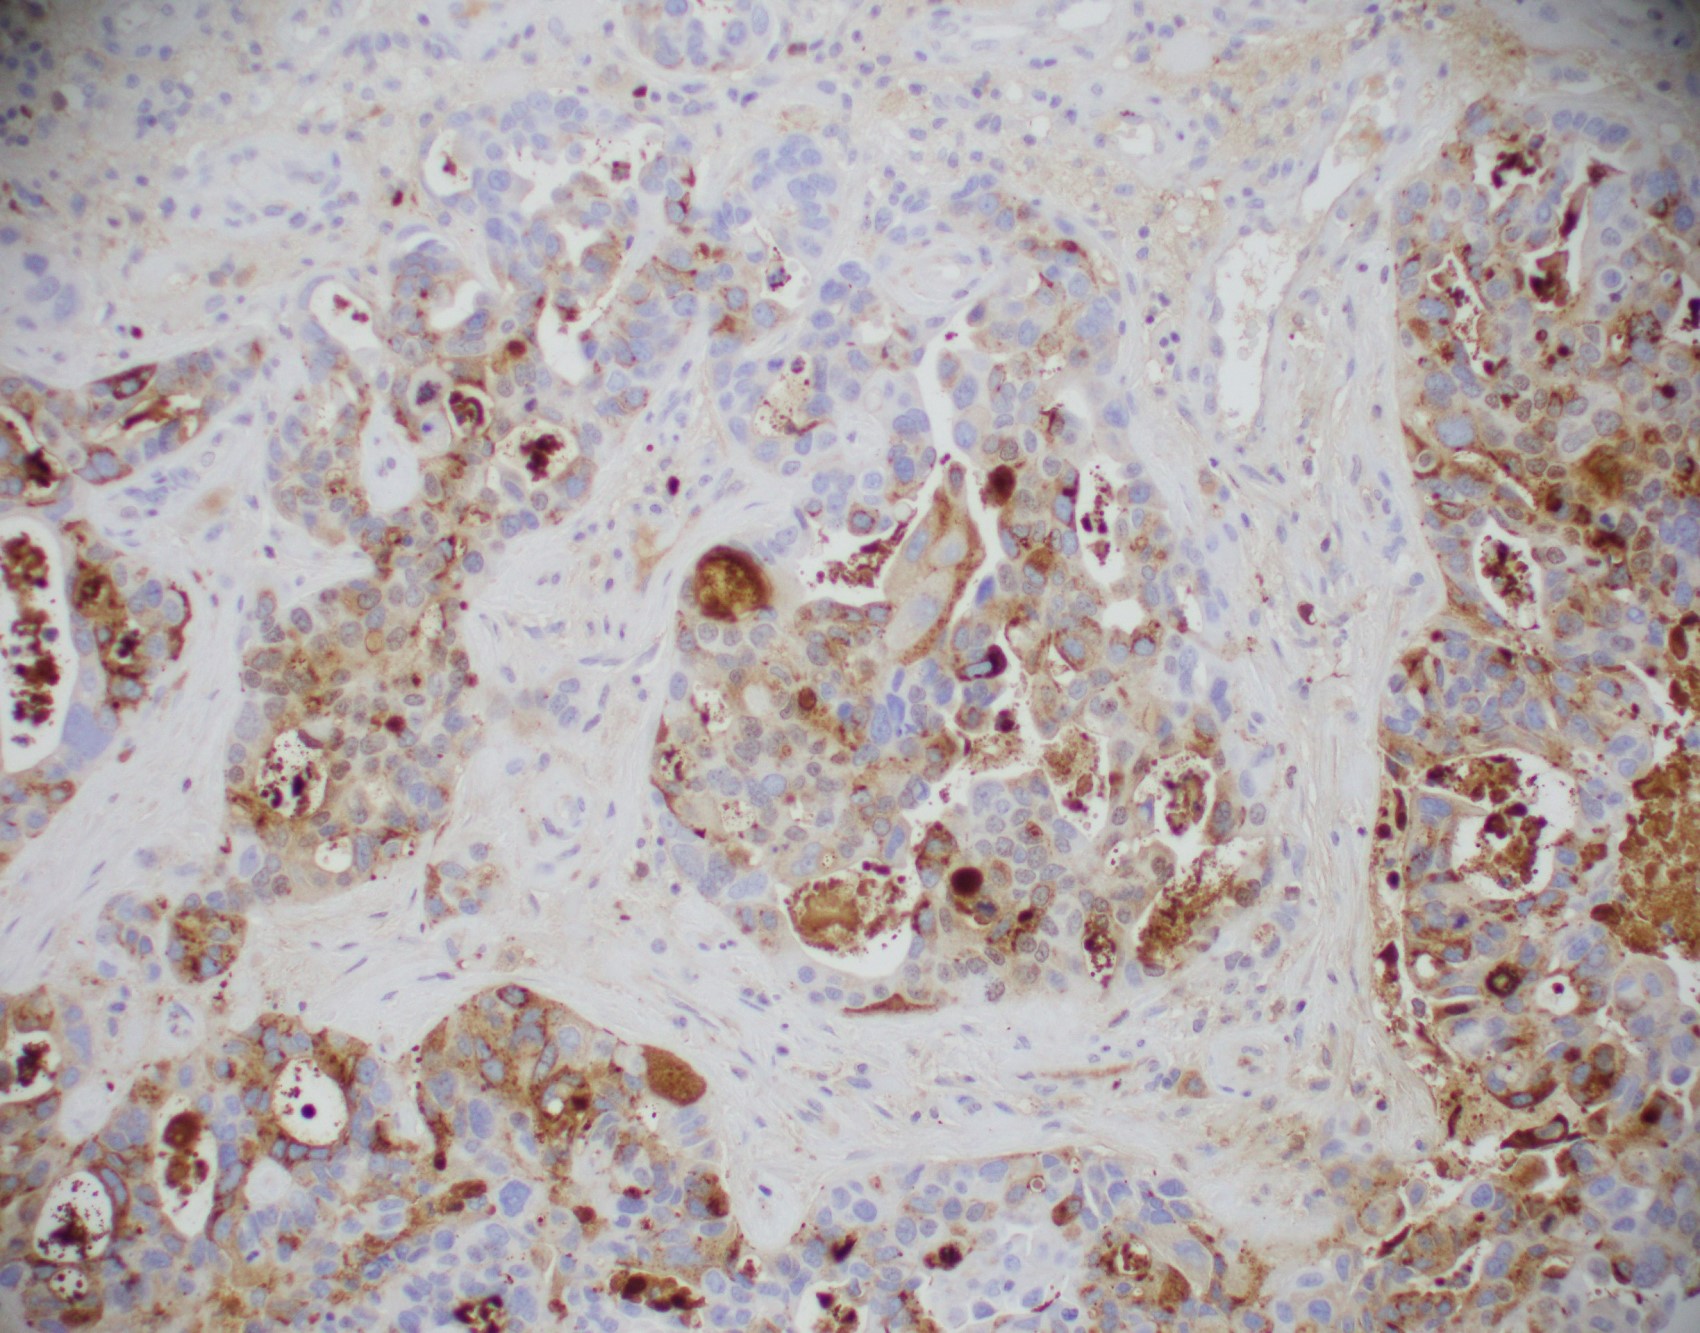

Microscopic (histologic) images

Contributed by Julie M. Jorns, M.D., Kristen E. Muller, D.O., Gary Tozbikian, M.D. and Emad Rakha, M.D.

Positive stains

- Luminal low molecular weight cytokeratins (CK8 / 18, CK19 and CK7 and pancytokeratins such as AE1 / AE3, CAM 5.2, MNF-116), EMA, E-cadherin, p120, ER (60 - 80%), PR (50 - 70%), HER2 (15 - 20%) (Am J Clin Pathol 2006;125:377)

- Invasive carcinoma with neuroendocrine differentiation:

- A proportion of IBC NST shows neuroendocrine differentiation of variable extent as determined by histological, histochemical and immunohistochemical analysis occurs but lack histologic features to classify as large cell or small cell neuroendocrine carcinoma or neuroendocrine tumor of the breast

- These tumors do not carry prognostic or clinical significance and they can be considered as variant (morphological pattern) of IBC NST (Hum Pathol 2003;34:1001)